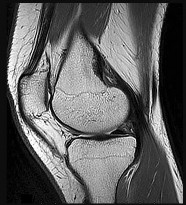

Question 2:

A 45-year-old female sustains a knee injury following a motor vehicle collision. Assuming the representative image demonstrates a medial tibial plateau fracture with articular depression (Schatzker IV), what is the most likely mechanism of injury?

Correct Answer: Varus force combined with an axial load

Explanation:

A Schatzker IV fracture involves the medial tibial plateau. The medial plateau is structurally denser and stronger than the lateral plateau, meaning fractures here typically require higher energy. The classic mechanism is a varus force combined with an axial load. In contrast, lateral plateau fractures (Schatzker I-III) are typically caused by a valgus force with an axial load. High-energy trauma to the medial plateau is also highly associated with injury to the peroneal nerve, popliteal artery, and ligamentous structures (like the ACL or LCL).